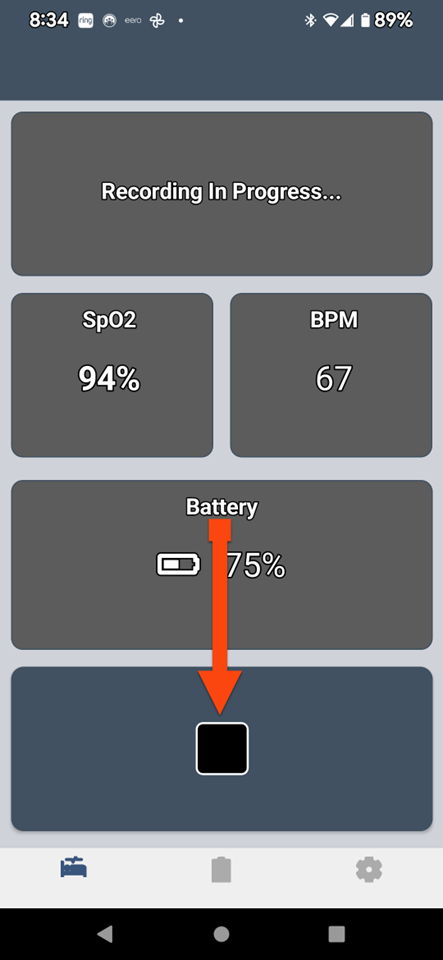

SLEEPIMAGE APP (Android)

SLEEPIMAGE APP (Android)

SLEEPIMAGE APP (Android)

SLEEPIMAGE APP (Android)

SLEEPIMAGE APP (Android)

SLEEPIMAGE APP (Android)

SLEEPIMAGE APP (Android)

SLEEPIMAGE APP (Android)

SLEEPIMAGE APP (Android)

SLEEPIMAGE APP (Android)

SLEEPIMAGE APP (Android)

SLEEPIMAGE APP (Android)

SLEEPIMAGE APP (Android)

SLEEPIMAGE APP (Android)

SLEEPIMAGE APP (Android)

SLEEPIMAGE APP (Android)

SLEEPIMAGE APP (Android)

SLEEPIMAGE APP (Android)

SLEEPIMAGE APP (Android)

SLEEPIMAGE APP (Android)

SLEEPIMAGE APP (iPhone)

SLEEPIMAGE APP (Android)

SLEEPIMAGE APP (Android)

SLEEPIMAGE APP (Android)

SLEEPIMAGE APP (Android)

SLEEPIMAGE APP (Android)

SLEEPIMAGE APP (Android)

SLEEPIMAGE APP (Android)

SLEEPIMAGE APP (Android)